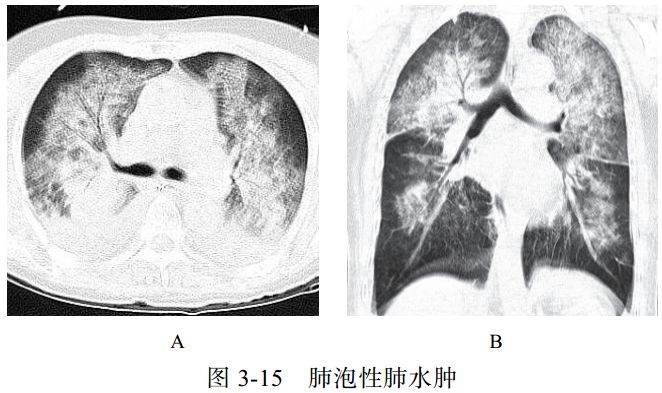

(一)肺泡性肺水肿

肺水肿病理上分为间质性肺水肿和肺泡性肺水肿,严重者常两种情况并存,心源性肺水肿居多。肺泡性肺水肿液体在肺泡内聚集呈片状,肺体积增大,有液体外渗,合并充血时渗液呈红色或棕色,急性期表现为气急、端坐呼吸、咳泡沫白痰或粉红色痰,可闻及湿啰音,可同时出现全身静脉压升高及肝脾大的表现。

影像学表现:

(1)典型蝶翼征(图 3-15A),两肺散布大小不等、密度不均、轮廓不清的片状模糊影(图 3-15B),局限性表现为一侧、一叶或局部的密度增高影。

(2)心源性肺水肿可见双侧上肺静脉扩张,心影增大,可合并胸腔积液、心包积液。